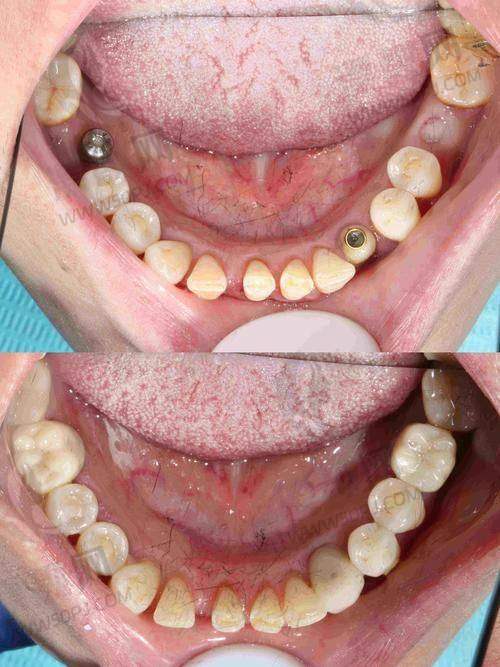

十、罗强口腔连锁种植院:懂你牙齿的城市种牙团队

这家口腔连锁在杭州多个区域设有分院,院长田宗从业十多年,曾进修于上海九院。机构主打精良数字导板进行种植诊断预判,尤其针对多年缺牙及顾虑术后调适的中年层客户建立专属治疗计划。 特色:术前数字模拟种植,全流程可视+追踪。 适合人群:错过黄金修复期、需高质量长期方案者。